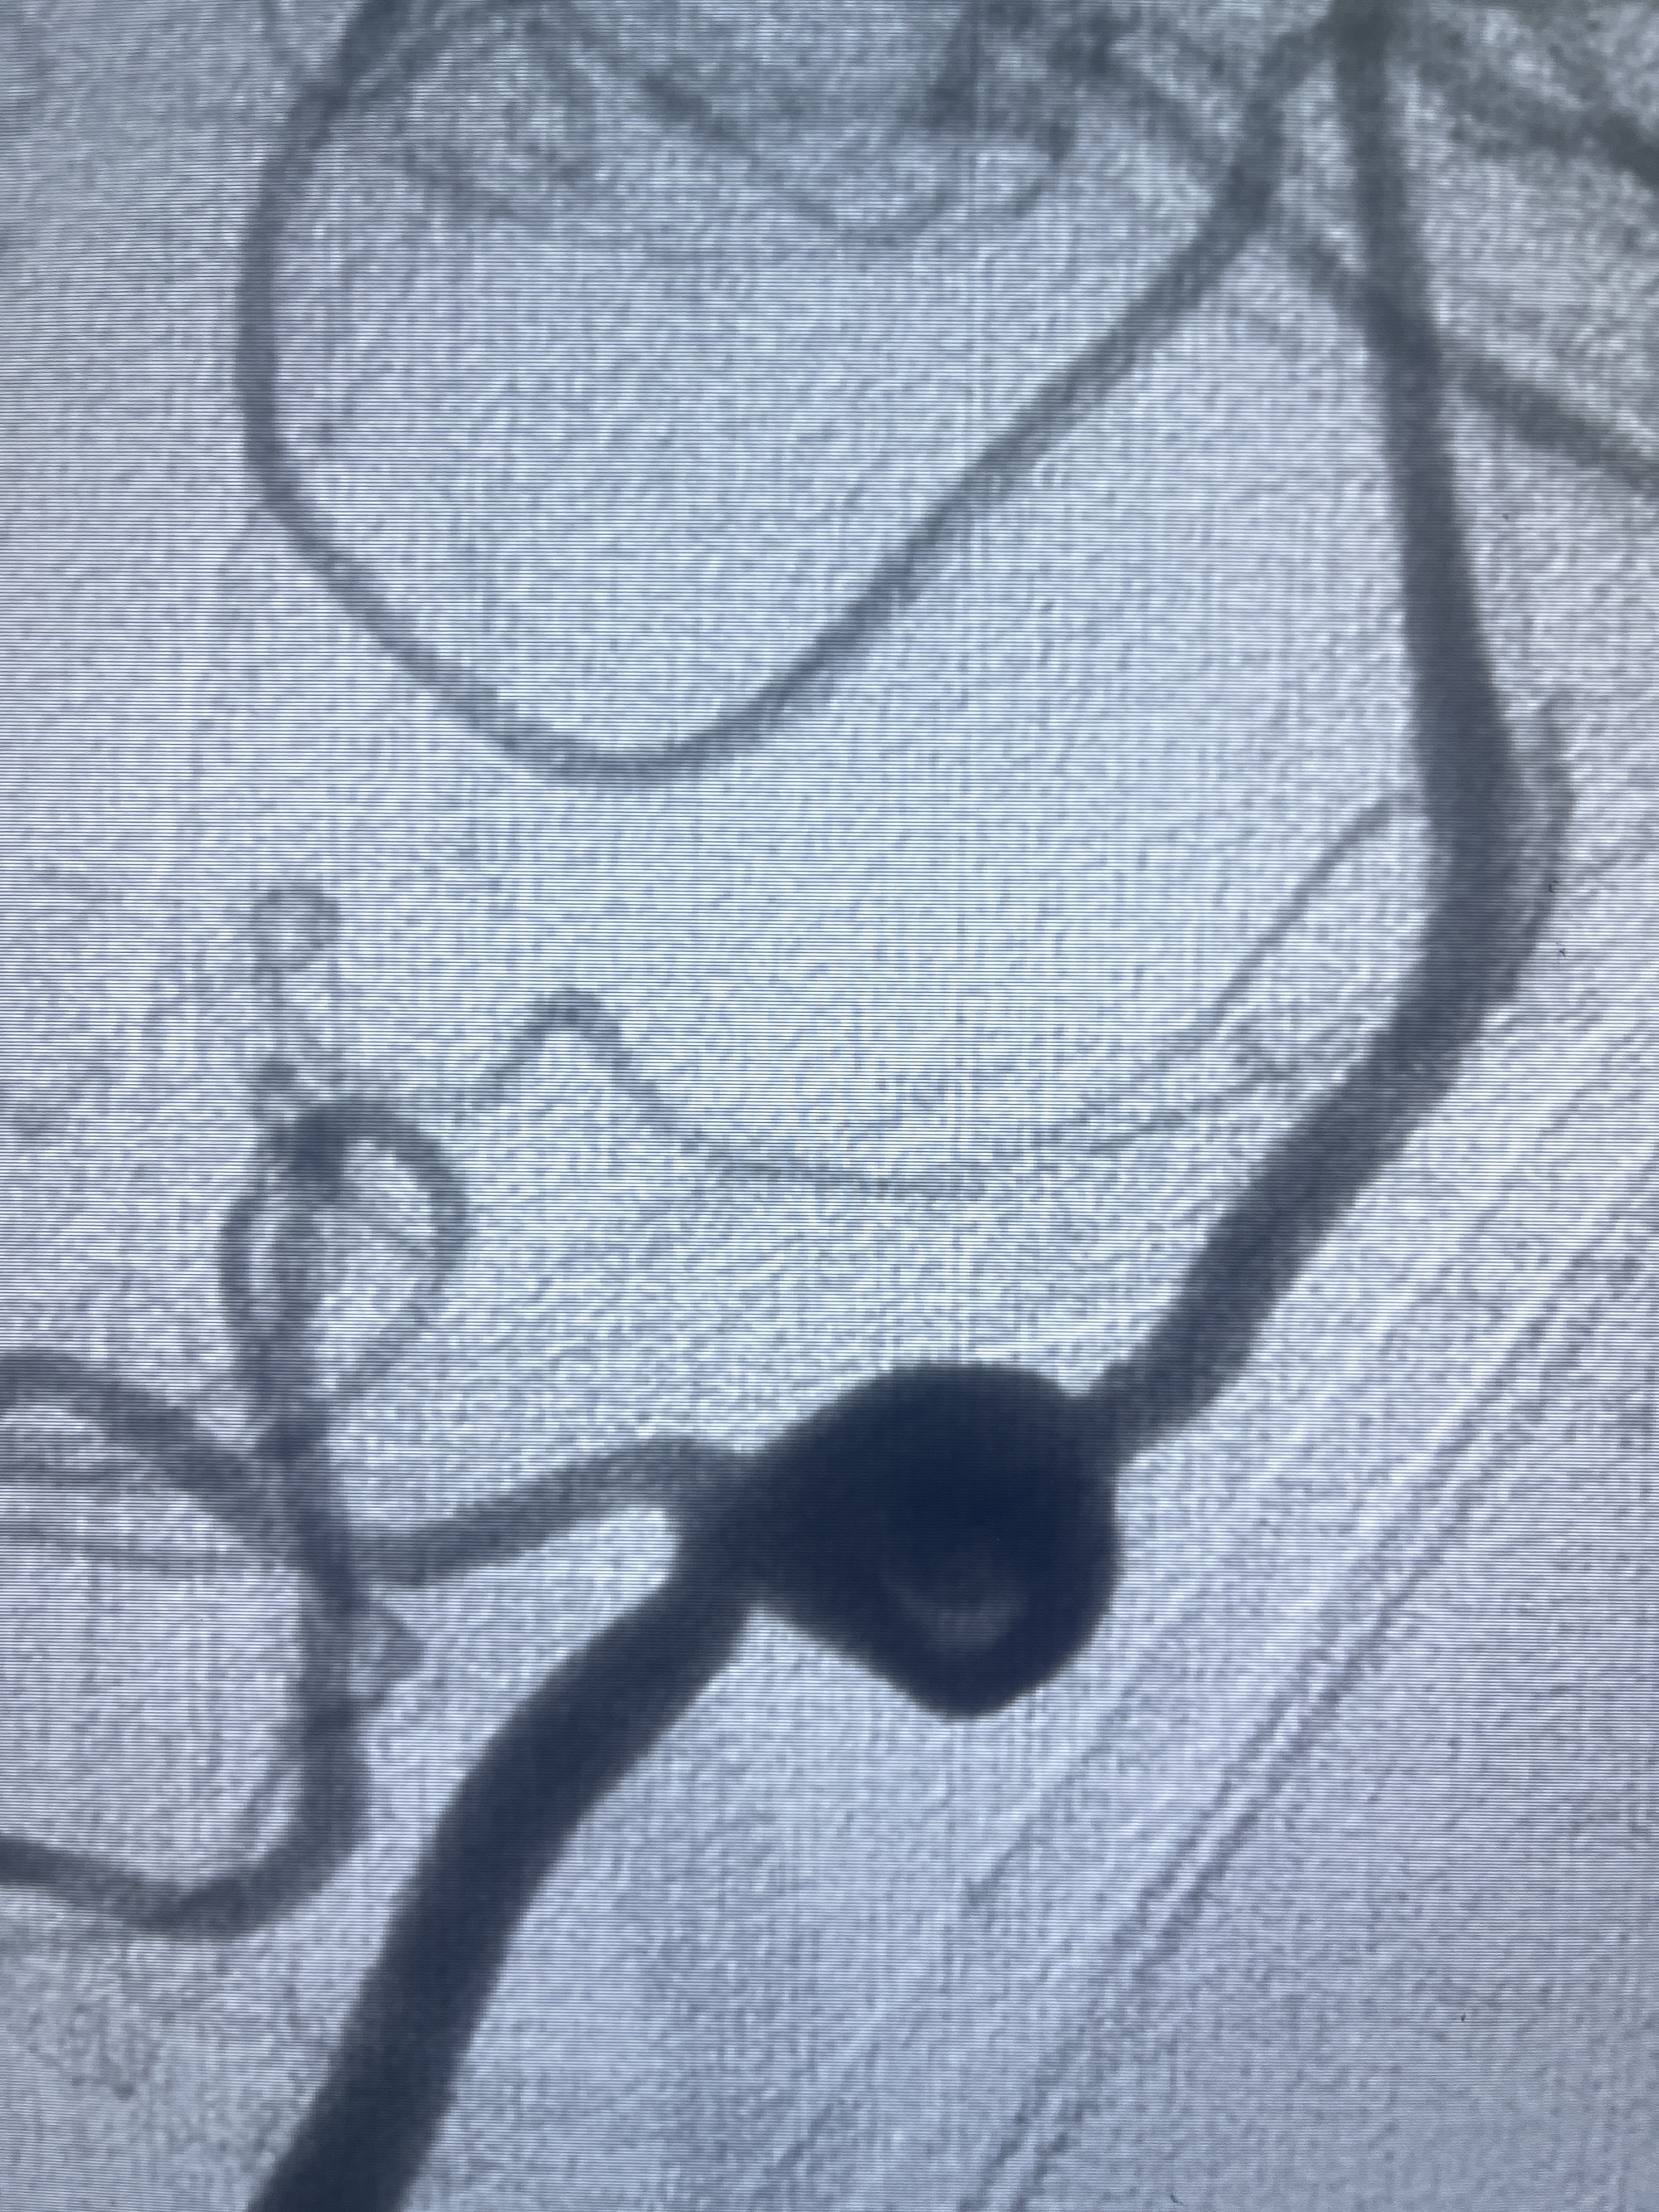

202.04.28脑血管造影:右侧大脑后动脉远段闭塞,右侧椎动脉V4段可见“囊状造影剂填充影”,大小7.64*7.65mm,可见PICA由动脉瘤发出;